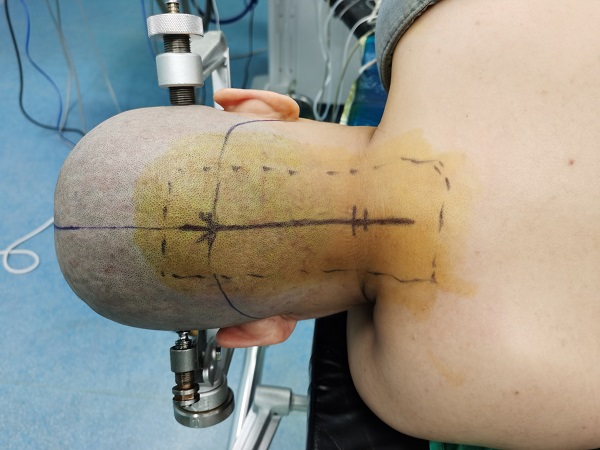

近日(ri),神經(jing)外科(ke)成(cheng)功完成(cheng)我(wo)院第30例腦幹腫瘤切除術(shù)。該患者爲(wei)一(yi)名(míng)37歲的(de)女性,因左側肢體(ti)活動(dòng)障礙入院治療,術(shù)中(zhong)見腫瘤位于(yu)延髓內(nei)部(bu),伴有(yǒu)出血,龐克軍主(zhu)任在(zai)顯微鏡下清(qing)除血腫,同時分(fēn)塊切除腫瘤,手術(shù)順利,術(shù)後(hou)患者肢體(ti)活動(dòng)恢複良好,按期出院。

自2017年(nian)總醫(yī)院成(cheng)功開展(zhan)第一(yi)例腦幹腫瘤手術(shù)以(yi)來,随着神經(jing)外科(ke)顱底顯微神經(jing)外科(ke)技(ji)術(shù)不斷(duan)成(cheng)熟,近幾年(nian)随着全國(guo)醫(yī)保聯(lian)網工(gong)作(zuò)的(de)推進(jin),外地來院就診的(de)腦幹腫瘤及(ji)複雜病例不斷(duan)增多(duo),腦幹腫瘤手術(shù)風險高(gao)、時間長(zhang),但昰(shi)在(zai)顯微神經(jing)外科(ke)技(ji)術(shù)成(cheng)熟的(de)前(qian)提下,随着神經(jing)內(nei)鏡咊(he)定向導(dao)航等(deng)新(xin)技(ji)術(shù)的(de)應用(yong),總醫(yī)院神經(jing)外科(ke)手術(shù)的(de)安(an)全性得到(dao)了(le)充分(fēn)保障。